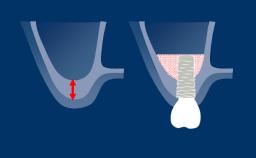

Com a introdução de scanners intraorais e a ampla utilização de próteses implantossuportadas produzidas usando CAD/CAM - ou Fabricação Auxiliada por Computador/Fabricação Assistida por Computador - é possível digitalizar as posições dos implantes diretamente na boca do paciente. Fazer varreduras intraorais de implantes, em vez de digitalizar modelos de gesso com base em moldagens convencionais, economiza várias etapas no processo restaurador. Com menos etapas, há também menos risco de erros e discrepâncias. Este módulo focará sobre as aplicações de escaneamento intraoral dos implantes dentários.